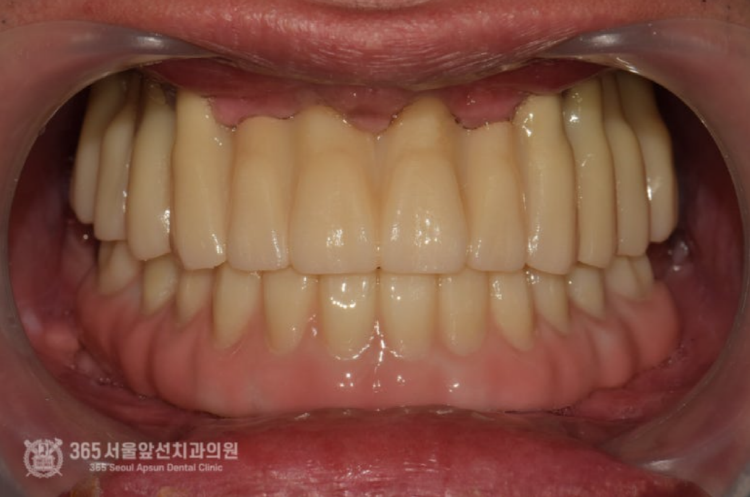

위 사진은 All on X라는 보철물 내부에 들어가는 금속구조물입니다. 정확한 용어로는 Mesostructure라고 합니다. (다른 환자분 케이스에서 사용된 금속구조물이지만 이해를 돕기위해 참고용으로 넣었습니다) All on X 보철물의 특징상, 단단한 강도가 매우 중요하며 보철물의 적합성이 매우 중요합니다. 따라서 정교한 작업이 필요하며 다소 번거롭더라도 여러번의 작업이 필요합니다. 촬영일시 : 2025.01.02. 아래쪽 보철물은 All on X 라고 하여 메탈 바가 들어가는 복잡한 방식의 보철물이기에 정확도가 생명입니다. 따라서 번거롭더라도 석고 모형 상에서 한번 맞춰보는 작업도 필요하기에 진행하였습니다. 위턱에 식립한 임플란트가 단단하게 굳었을때 쯤 임플란트에 치유지대주라는 단추를 연결합니다. 이제 슬슬 본을 떠도 되겠습니다. 양측 어금니 부위에 뼈가 매우 부족하여 상악동 거상술을 진행하였던 부위도 뼈가 생성되는게 관찰됩니다. 아래턱 보철물이 입안에 위치된 상태입니다. 아래만 맞춰봤는데 환자분은 벌써부터 기대감이 대단하십니다. 이 단계쯤되면 저도 두근두근합니다ㅎㅎ 위아래 보철물이 모두 장착된 상태에서의 파노라마 엑스레이 사진입니다. 제가 치료해드렸지만 제가 봐도 만족스럽습니다 ㅎㅎ 촬영일시 : 2025.01.15. 촬영일시 : 2025.01.15. 위아래 보철물이 모두 들어간 상태의 구강내 사진입니다. 환자분은 치료가 끝나고 눈물을 글썽글썽하셨습니다. 전체 임플란트 치료는 그만큼 요구되는 수준이 높고 의사도 힘들고 환자분들께서도 힘들지만 치료가 마무리 되고 나면 기억에 많이 남는것같습니다. 오늘도 매우 뼈가 좋지 않았던 환자분의 고난이도 치료 증례를 소개해드렸습니다. 앞으로도 좋은 치료 증례로 도움이 될 수 있게 노력하겠습니다. 지금까지 365일 열린 가까운 서울대학교 치과병원을 지향하는 주안동치과 365서울앞선치과였습니다. 감사합니다. [ 치료기간: 2024년 7월3일 ~ 2025년 1월 15일 ] ※ 365서울앞선치과의원의 모든 포스팅은 각 진료과 의료진이 직접 작성합니다. 365서울앞선치과의원 블로그의 임상 케이스 게시물은 환자분께 의학적으로 정확하고 상세한 정보를 드리기 위해 각 진료과 의료진이 직접 작성하며, 모든 증례 사진은 본원 의료진이 직접 시술한 증례를 촬영한 것으로, 의료법 제23조, 제56조에 의거하며 환자분의 동의를 얻어 포스팅에 사용하였습니다. 또한 해당 케이스는 본 환자분의 치료 결과이며, 환자 상태에 따라 치료의 결과는 달라질 수 있습니다. |